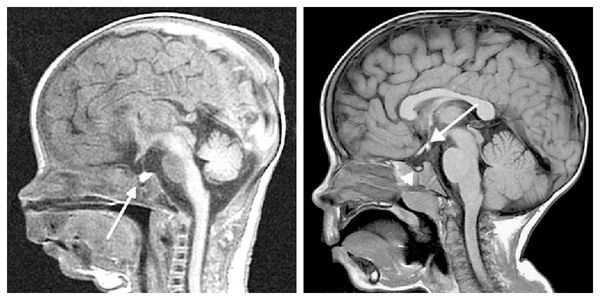

- При перинатальном поражении головного мозга ( гипоксии, внутриутробном инфицировании, кровоизлиянии при родах) часть клеток головного мозга погибает, а оставшиеся повреждены и не формируют между собой новые связи. Взаимодействие между нейронами — необходимое условие для того, чтобы сформировались речевые навыки. В зависимости от пострадавших зон головного мозга, возникают различные нарушения. Например, если повреждена зона Вернике, то ребёнок не понимает речь и у него не формируется пассивный словарный запас — он не запоминает названия предметов и действий. Если пострадала зона Брока, то не пополняется активный словарный запас и ребёнок не произносит слова.

- При гидроцефалии повышенное внутричерепное давление приводит к расширению желудочковой системы с истончением белого вещества головного мозга. Происходит сдавление проводящих путей, которые связывают различные зоны мозга. Нарушается взаимодействие речевых зон, необходимое, например, для ответа на вопросы. Когда ребёнку задают вопрос — "понимает" его зона Вернике. Она связывается по проводящим путям с зоной Брока, которая "формирует" активный ответ, и ребёнок отвечает. Но если пострадали проводящие пути, то ребёнок не отвечают на вопросы, хотя понимает речь и спонтанно произносит слова. Если повреждены проводящие пути, обеспечивающие нервами речевую мускулатуру, то у ребёнка нарушается дикция.